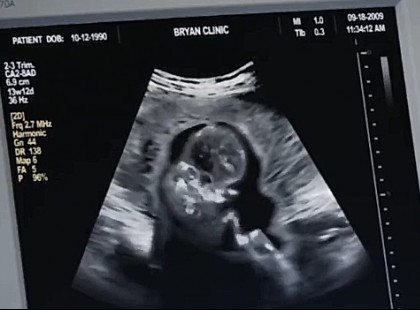

Nekem ne legyenek unokáim egy falusi libapásztortól!” – jelentette ki a gazdag üzletember, majd kitagadta a fiát, amikor megtudta, hogy a faluról származó menyasszonya HÁRMASIKREKKEL terhes!

Miközben Mariann három gyermeket hozott világra a szülőszobán, férje, József és annak fiatal szeretője, egy ördögi „meglepetéssel” készültek... A férfi elvált tőle a háta mögött, majd kidobta a saját lakásából is! De aztán... jött egy olyan váratlan fordulat, amitől megrepedt a galambpár rózsaszín álma, és nem várt pofon csattant a „szerelmesek” arcán… ??? ? A teljes történet – a fotó alatti első kommentben ??

Mit gondolt egyáltalán a nőgyógyászod?!” – üvöltötték az orvosok egy 56 éves asszony szülése közben. De amikor meglátták, KIT szült... mindenki lefagyott a döbbenettől ??? A rekkenő hőség úgy ült a falu fölé, mintha maga a pokol fújt volna forró levegőt a háztetőkre. A csendet csak a tücskök ciripelése és a fák között bujkáló szél zizegése törte meg – mígnem egy mentőautó vijjogása kettévágta a levegőt. A poros földúton fékezett, egy rozoga parasztház előtt állt meg. A mentős Ludmilla – izzadtan, remegő kézzel – ugrott ki az autóból: – Gyerünk! Alig bírja már! Lajos azonnal kirohant a házból, karjaival átkarolta feleségét, Kovács Máriát, aki fájdalomtól görnyedve suttogta: – Ha bármi történne… vigyázz rájuk, Lajos… tartsd rajtuk a szemed... Az ujjai jéghidegek voltak, a tekintete üveges – Ludmilla csak suttogni merte: – Istenem... ez túl nagy kockázat… Mária már a nyugdíj kapujában állt, de most életet készült adni. A terhessége maga volt az orvosi csoda – vagy őrültség. A szülés előtt azonban még senki sem sejtette: az igazi dráma csak most kezdődik... A városi kórház műtőjében szinte az összes ügyeletes orvos összegyűlt. Ritka esemény volt ez: egy 56 éves asszony szülése önmagában is szenzáció. Az orvosok suttogva, aggodalmasan figyelték a monitorokat. – Ez... ez hogy lehetséges? – kérdezte egyikük döbbenten. – Miért nem szakították meg időben a terhességet? – Mit képzelt a nőgyógyásza?! – robbant ki a főorvos. – Ez őrültség! De ekkor megszólalt a szülészet legendás alakja, a deres hajú dr. Szabó Leonárd: – Elég! Most koncentráljunk. Egy élet forog kockán. A levegő vibrált a feszültségtől. A műtét elindult, minden másodperc egy örökkévalóságnak tűnt. Majd végül… felhangzott egy újszülött első, rekedt sírása. A személyzet arca felderült… de csak egy pillanatra. – Várj csak… – szólalt meg halkan az egyik szülésznő. – Ez… ez nem stimmel… Jegor doktor előrelépett, hogy megnézze a babát, majd egy pillanat múlva ösztönösen hátrált, mintha valami földöntúlit látott volna. – Te jó ég… Ez… ez lehetetlen… – suttogta. A műtőre dermesztő csend borult. Mindenki egyszerre némult el. Amit láttak… azt senki nem akarta kimondani. Folytatás a kép alatti első hozzászólásban... ???